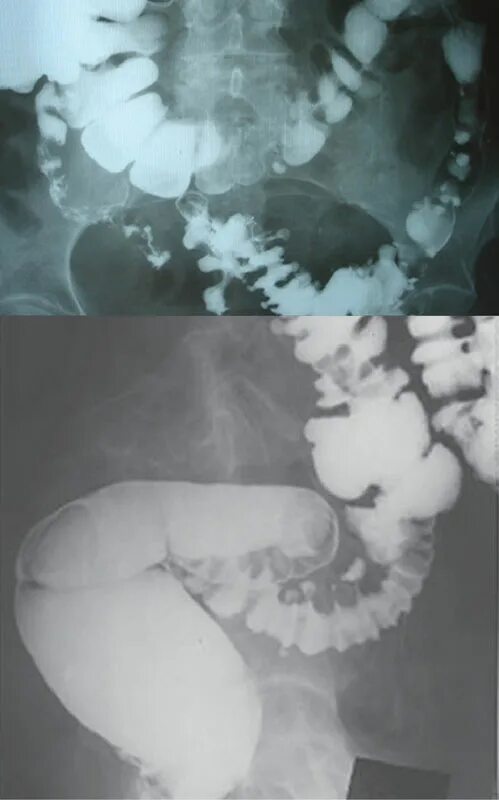

Дивертикулез толстой кишки рентген. дивертикул сигмовидной кишки рентген. дивертикулез толстого кишечника рентген. ирригоскопия кишечника дивертикулы.